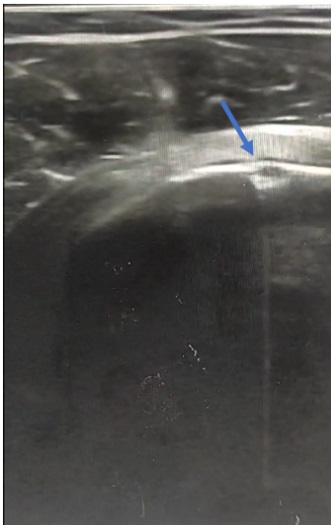

• Se realizó una ecografía, en la que se apreció una solución de continuidad en la cortical del húmero que hizo pensar en una avulsión del tendón del músculo subescapular.

• Diagnóstico diferencial: tendinitis o rotura de cualquier músculo del manguito de los rotadores (con mayor probabilidad del músculo subescapular, de acuerdo a la exploración física), calcificaciones ligamentosas del manguito de los rotadores, artritis glenohumeral o acromioclavicular, bursitis subacromial, fractura ósea.

• Juicio clínico: avulsión del tendón del músculo subescapular del hombro derecho.